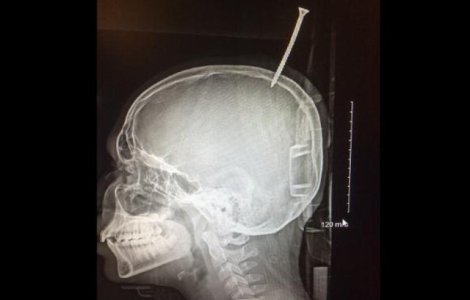

Darius Foreman, un baiat in varsta de 13 ani din Maryland, a ajuns de urgenta la spital, sambata, dupa ce a cazut in timp ce construia o casuta in copac si si-a perforat capul intr-un surub de 15 centimetri.